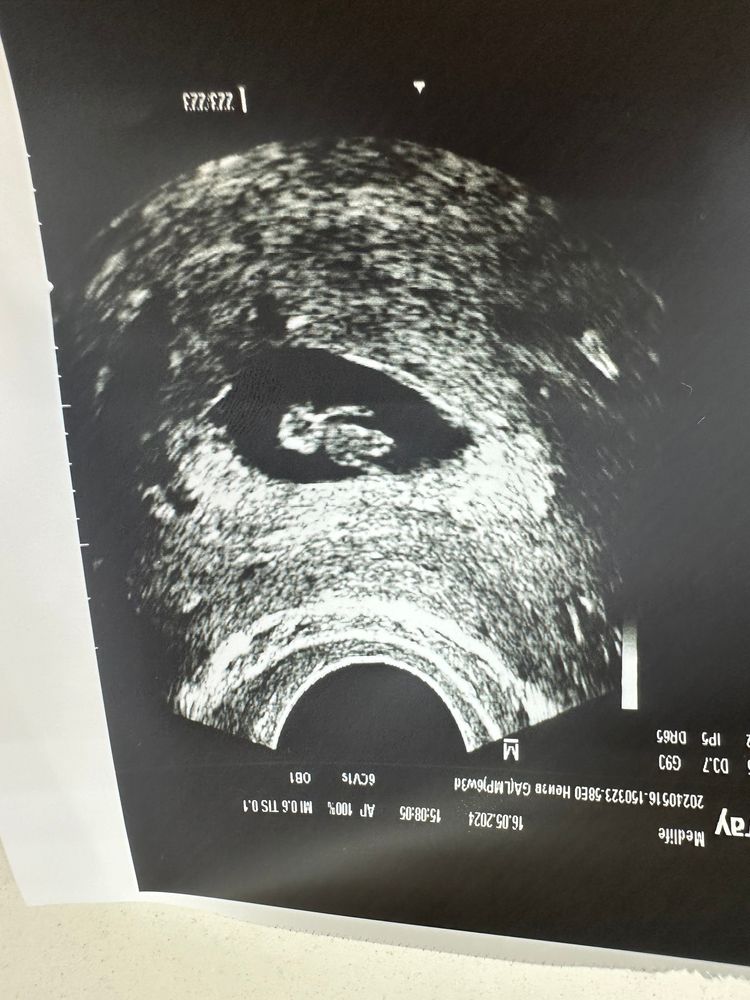

27 ДПП / 6+3 УЗИ ❤️

Какой красавчик, ттт, растите , будьте здоровы и пусть всё протекает прекрасно